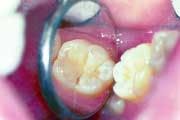

Since the introduction of fluoridation, outwardly detectable decay has been dramatically reduced. Because of the strengthening that fluoride creates in the outer layer of tooth enamel, the pattern of decay has changed. Rather than large areas of a tooth surface succumbing to the attack of plaque acid, decay now appears as small discreet areas, often undetectable to the dental probe, yet visible as a color change inside the tooth under magnification. Dentists have observed this change, and have continued to develop a science based on prevention and protection and the continuing miniaturization of all treatment procedures. New filling and restorative materials and techniques also have been developed. The new techniques require early and aggressive investigation of stains, the targeted removal of unsound tooth structure vs. the indiscriminate removal of sound tooth structure, and bonded restorations rather than traditional "drill, fill, and bill" approaches.

Patients are showing a great demand for conservative dentistry. Micro air abrasion has opened up a whole new method of treatment for them that preserves far more tooth structure than was ever previously possible. The resulting surfaces also are better prepared to receive and retain bonded restorations, compared to previous traditional methods of preparation.